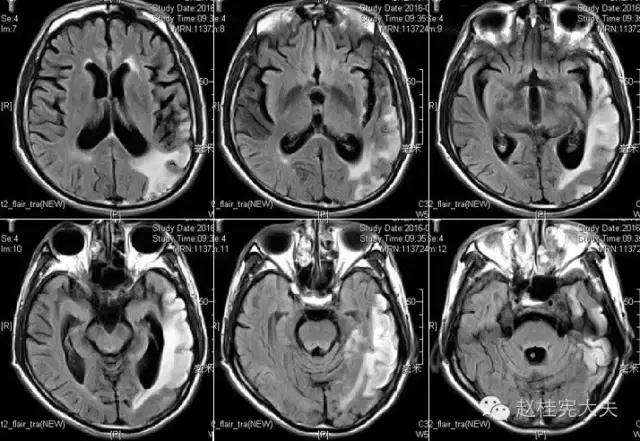

入院前1天的头颅CT:

定位诊断:混合性失语,定位于左侧大脑半球语言中枢(运动和感觉),右侧中枢性面舌瘫,定位于左侧面神经核团以上,右侧上下肢肌力下降,病理征阳性,定位于左侧锥体束。感觉、视野查体无法配合,暂无相应定位考虑。综合考虑,定位于左侧大脑中动脉分布范围。头颅CT:左侧颞叶片状低密度影,左侧大脑中动脉下干支配区,支持临床定位。

定性诊断:结合57岁,男性,急性病程,逐渐加重,进展性右侧肢体无力、混合性失语。头颅CT:左侧颞叶片状低密度影。脑梗死为首先考虑,左侧大脑中动脉支配区,大动脉粥样硬化型。尽管患者本人无高血压、糖尿病等危险因素,但患者母亲有中风、糖尿病史,存在家族中风危险因素,故待完善血生化及血管等卒中危险因素筛查。入院后继续急诊抗血小板、降脂稳定斑块及脑保护治疗。

完善检查,头颅MRI回报:左侧颞顶枕叶急性梗死灶。

患者的磁共振影像不符合脑血管病的血供分布,跨了大脑中动脉和大脑后动脉范围,且病灶偏皮层分布。大脑前、中、后动脉血供分布(横断面)见下图

这不是一个真的“脑卒中”,而是一个“卒中样发作”。